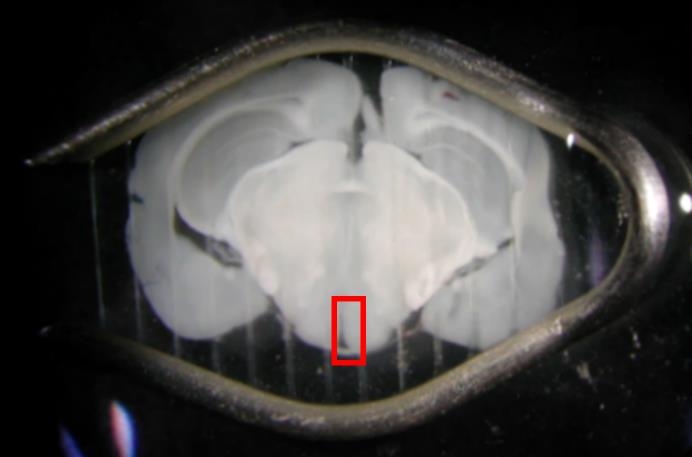

安楽死させたマウスから脳を取り出し、マイクロスライサーという装置で0.15mmの厚さに切ってから、その脳切片を動かぬように固定します(図1)。